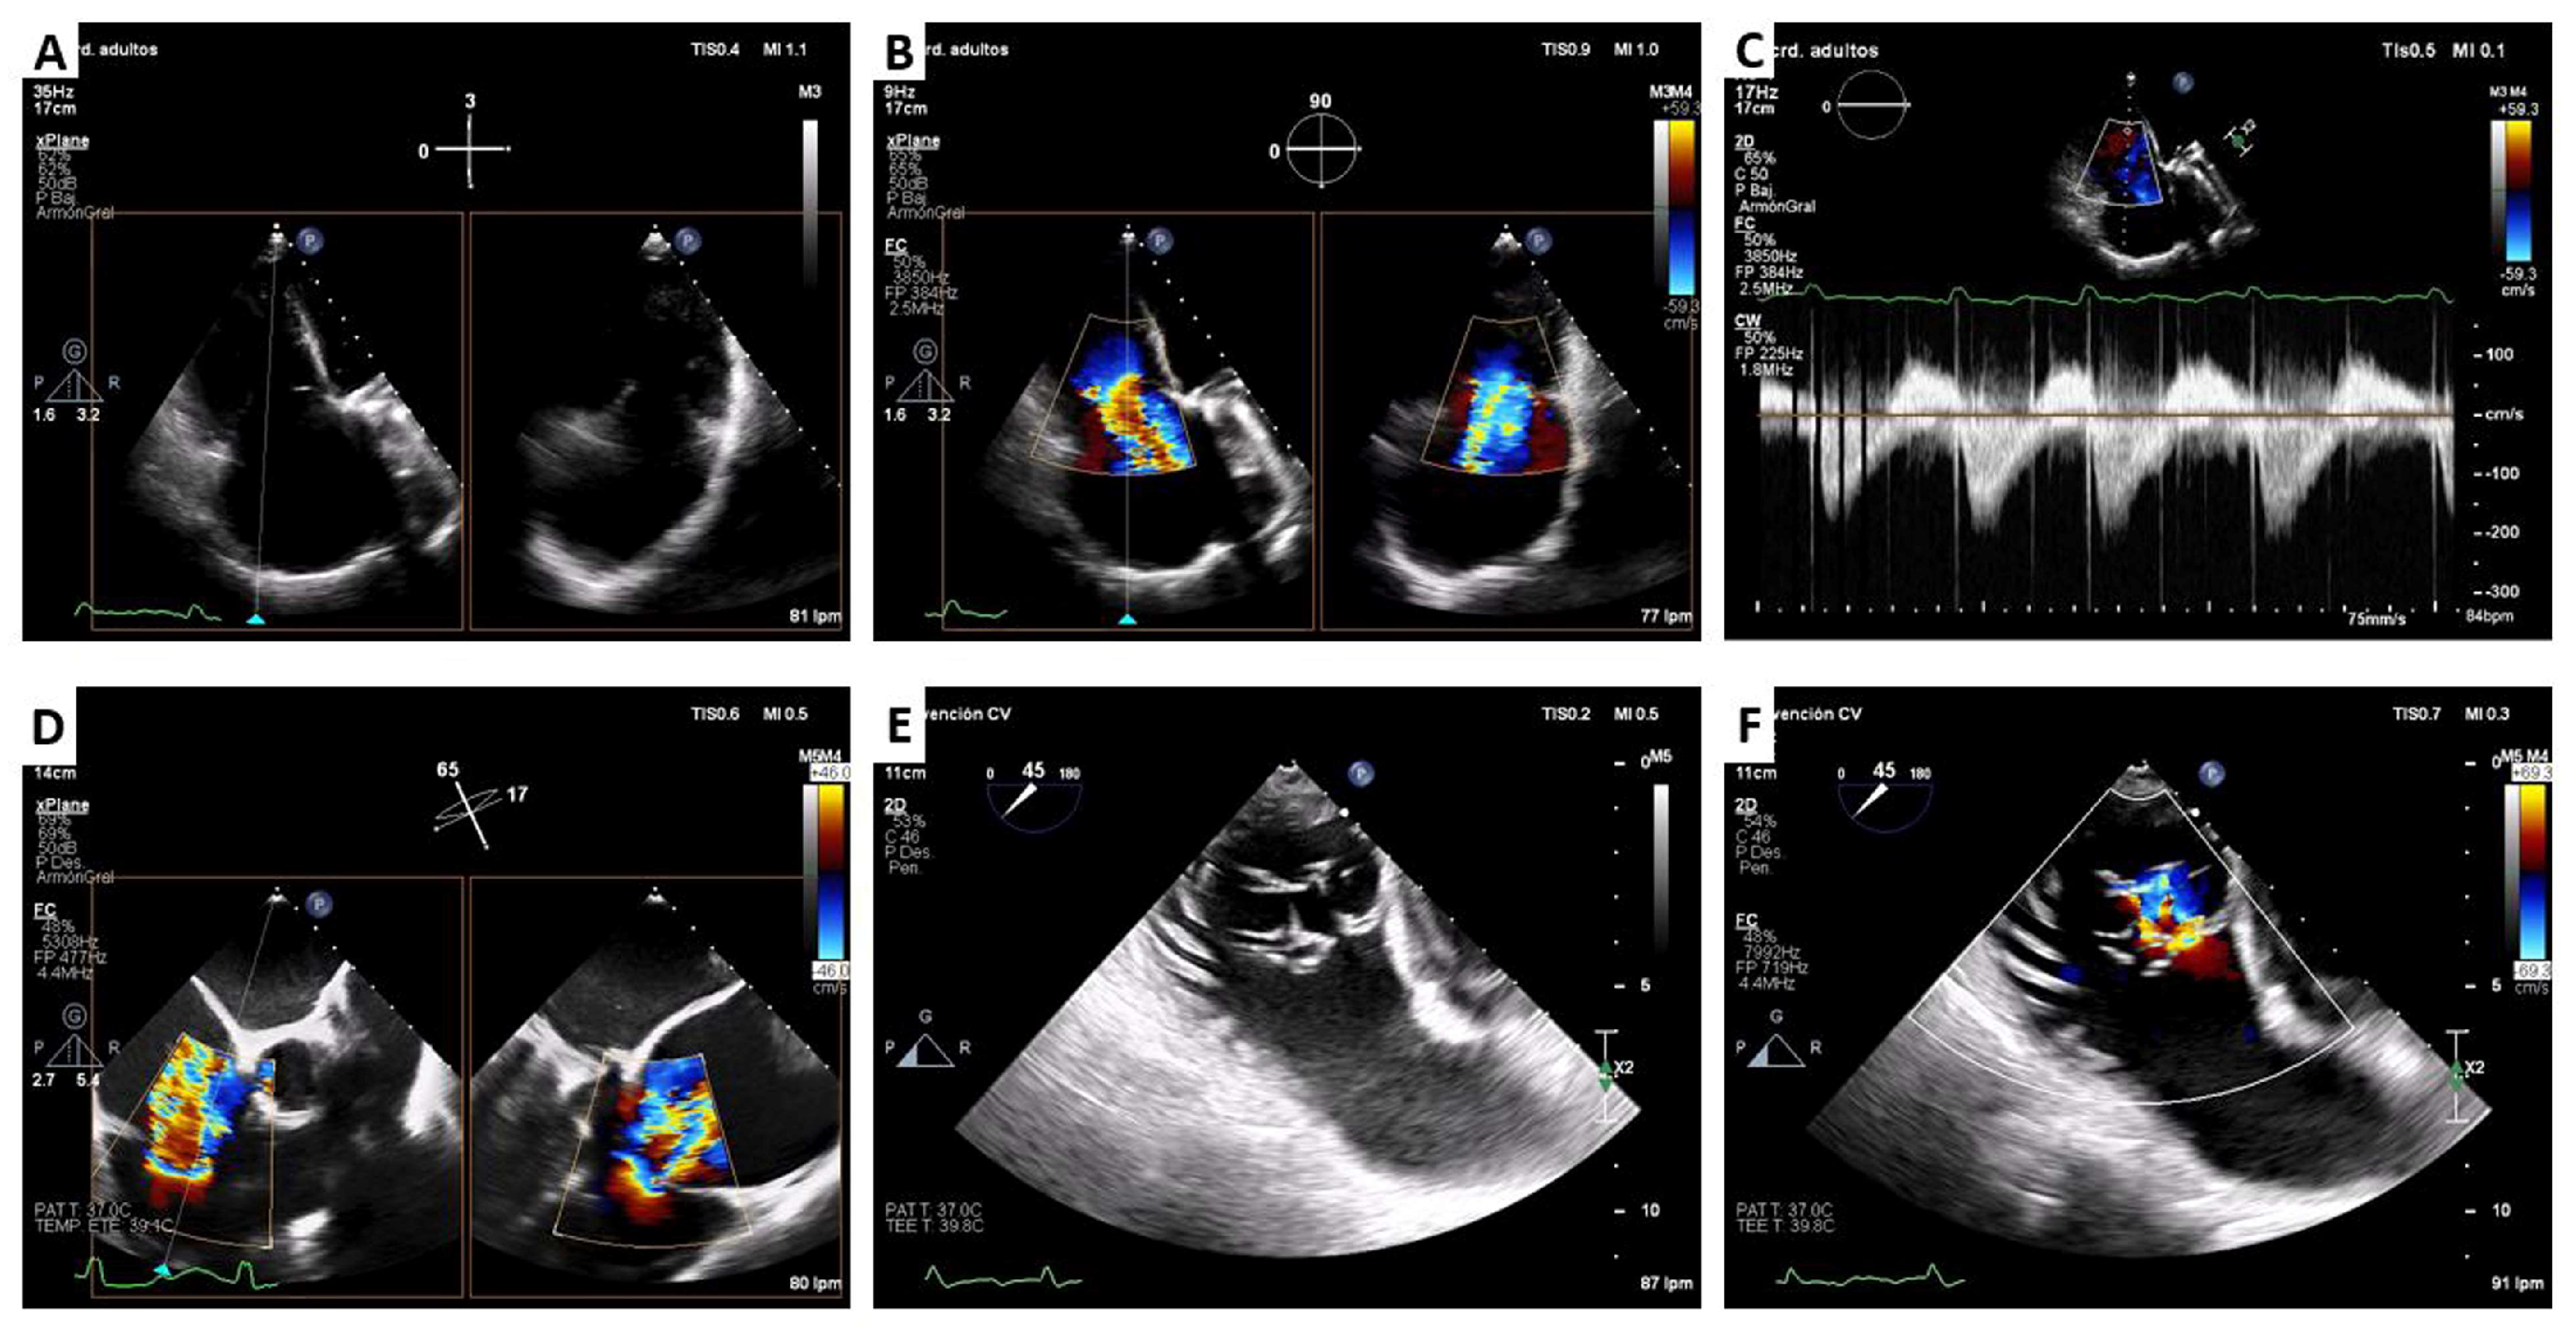

2. Cardiovalve Cases

4.2. Cardiovalve